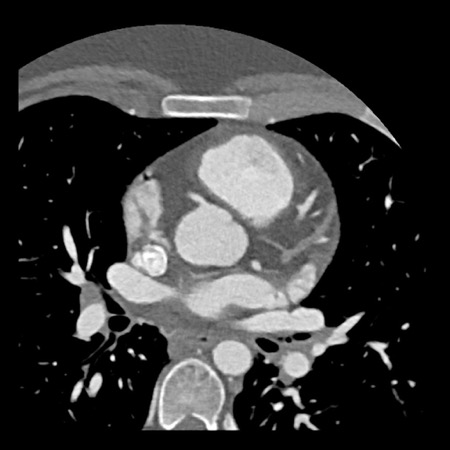

case 4 – CAD-RADS 3/P1/I+ thrombus left ventricle

The findings are:

- Moderate (50-69%)

stenosis in the proximal LAD caused by a non-calcified plaque. - Variant of

sinoatrial (SA) nodal artery. The artery usually arises from the RCA as a second

branch after the conus artery, however in this case it arises from the LCX,

courses behind the aorta, anastomosing with the right atrium and with a small

branch supplies the SA-node of the heart. - Thrombus in the

apex of the left ventricle. - CTP was performed

in this patient. CTP showed a perfusion defect at stress imaging in the

territory of the LAD (I+), at rest no perfusion defect was visible.

This patient classifies as CAD-RADS 3/P1/I+, which means

this patient requires further investigation.